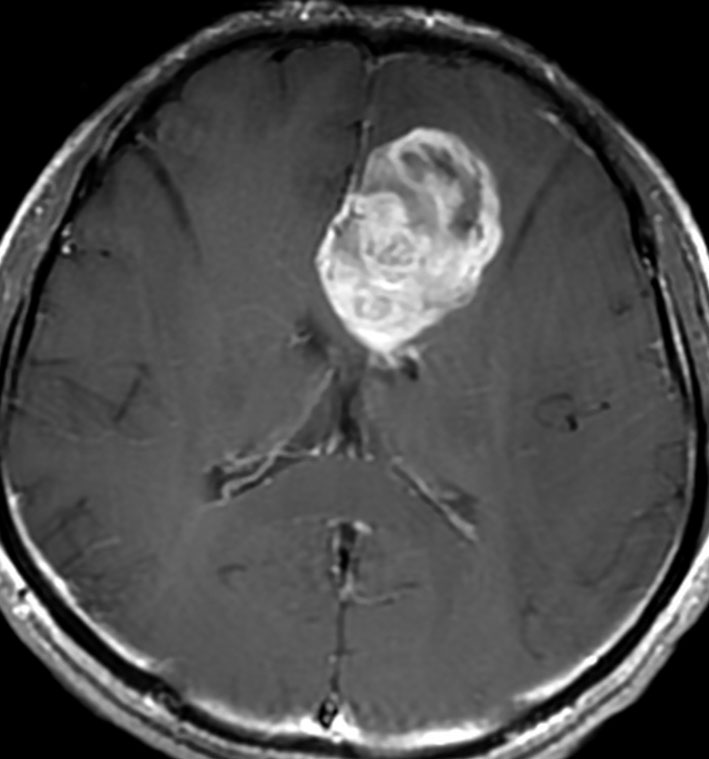

左上前頭回のびまん性グリオーマ diffuse glioma です。手術でほぼ全摘 gross total removalして54グレイの放射線治療とテモゾロマイド化学療法をしました。病理診断は,oilg 2陽性,1p/19q染色体の欠失はない退形成性乏突起星細胞腫 グレード3とされました。全体的にはグレード2であるとの病理医の意見もありましたし,当時は北大病院でもIDHの正確な分子病理診断は行われていませんでした。

5年後です。上前頭回の病巣は落ち着いていましたが,初回にはなかったはずの場所,脳梁前方に急激な再発増大を生じました。また手術で全摘出 gross total removalして,かなり絞った領域に60グレイの放射線治療とテモゾロマイド,アバスチンの投与をしました。病理診断は,IDH wild-tpye, 1p/19q non-codel, MIB 40%, ATRX positive, MGMT negativeの膠芽腫でした。

その後またしばらく寛解継続できました。